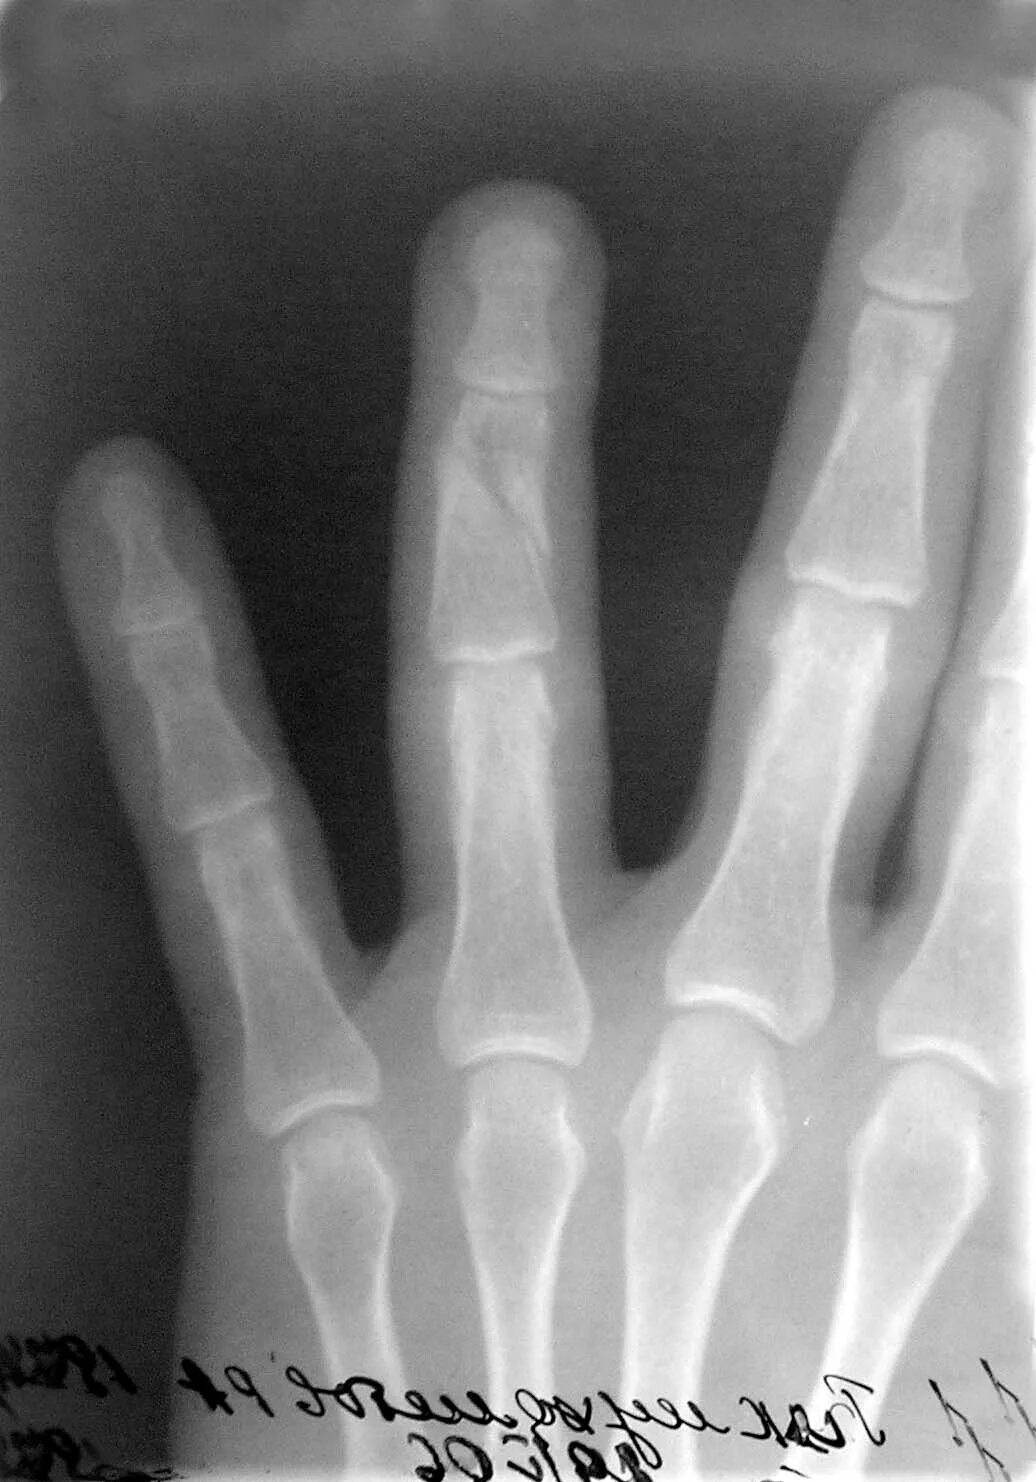

Трубчатые пальцы